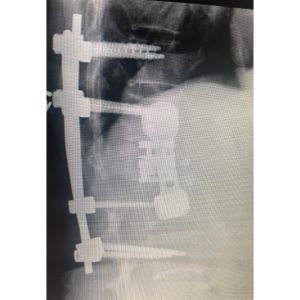

She was taken to surgery about 4 1/2 years ago and the entire L1 vertebrae and tumor was surgically removed from the front and back with the help of a vascular surgeon. I had to place extensive hardware from the front and back to support the missing vertebrae. She recovered well. Recent CT scans showed no further cancer in the spine. (Photos 3-5.)